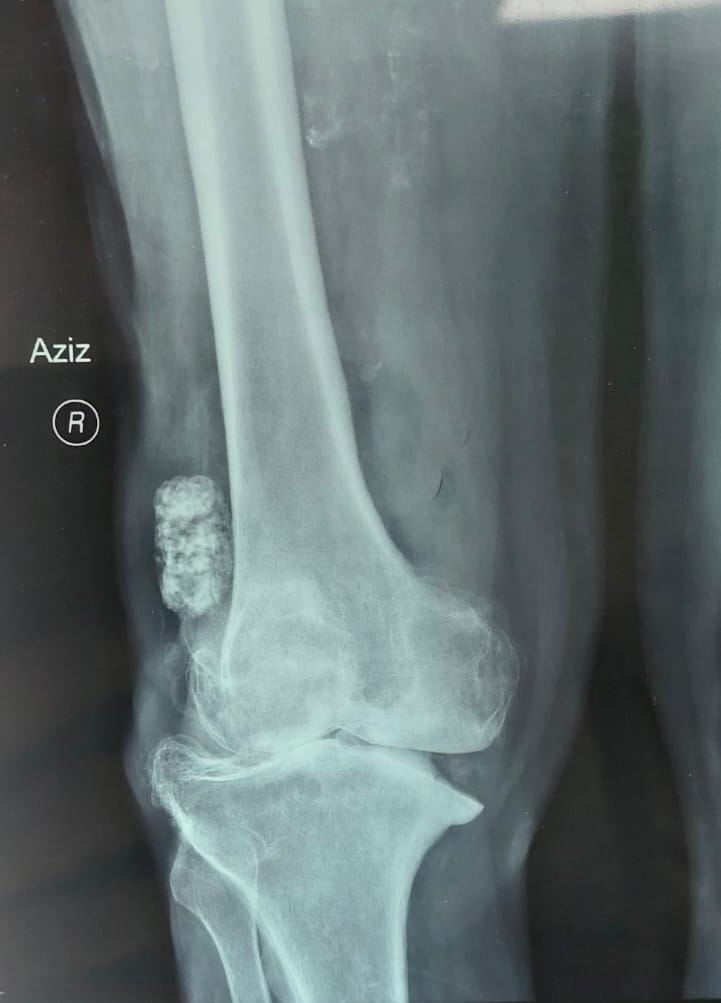

اجرى فرق طبي جراحي عملية جراحية نوعية لرجل يبلغ من العمر ٦٥ سنة يعاني من سوفان شديد وعدم استقرار في الركبه وصعوبة في الحركه وتقوس في الساقين و بعد إجراء الفحوصات الشعاعية اللازمة

اجريت له العملية الجراحية